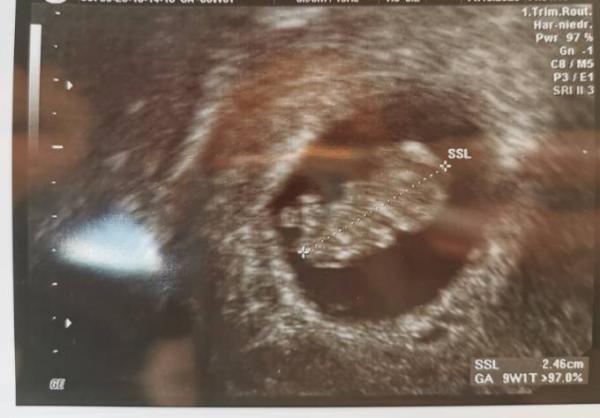

Magst du das andere Bild auch mal zeigen? Willst du es wissen für Ramzi?

Genau. Einfach aus Spaß an der Freude!

Bild zu